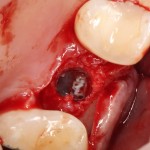

При наличии соответствующих условий возможно проведение операции немедленной имплантации одновременно с синуслифтингом (рис 54, 55, 56):

Рисунок 54, 55, 56. Проведение операции синуслифтинга одномоментно с удалением зуба и установкой импланта.

В ходе воспалительного процесса, при излишне травматичном удалении или вследствие анатомических особенностей нередко отсутствует вестибулярная стенка лунки зуба – в дальнейшем, это может привести неблагоприятному эстетическому и функциональному результату. Костный фрагмент, получившийся при создании доступа в верхнечелюстную полость, можно использовать для пластики внешней стенки лунки (рис 57, 58, 59):

Рисунок 57, 58, 59. Пластика внешней стенки лунки костным фрагментом при немедленной имплантации и синуслифтинге: слева – этап синуслифтинга и имплантации, в центре – пластика внешней стенки альвеолярного отростка методом аутотрансплантации костного фрагмента, справа – этап установки формирователей десны через 3 месяца после имплантации.